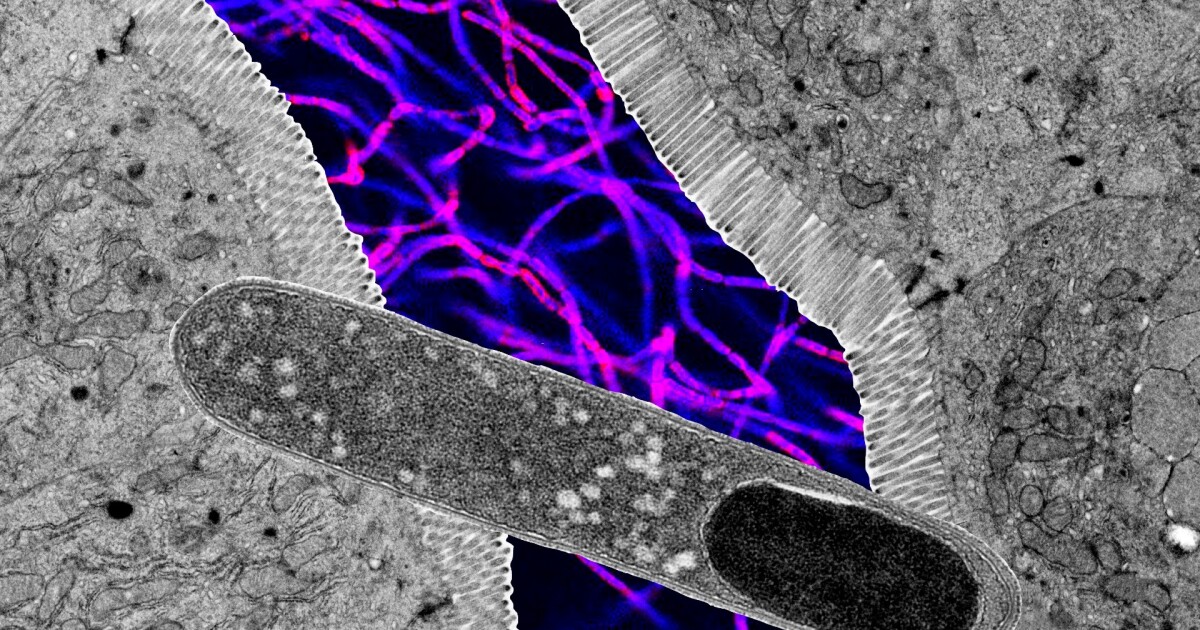

However, researchers at the University of Utah (U of U) say they have succeeded in whittling down about 100 bacteria suspected of fighting weight gain to just one that really does: Turicibacter.

In their study, mice that were fed a high-fat diet and were also given Turicibacter saw reduced blood sugar, lower levels of fat in the blood, and less overall weight gain compared to a control group.

Somewhat paradoxically, Turicibacter bacteria also produce lipids (fats) in the gut. But the molecules they produce actually tamp down the rise of ceramides, even in the face of high-fat consumption. Furthermore, when a high-fat diet is consumed, it drowns Turicibacter, eliminating its protective effects. In humans with obesity for example, Turicibacter levels in the gut have been found to be reduced.